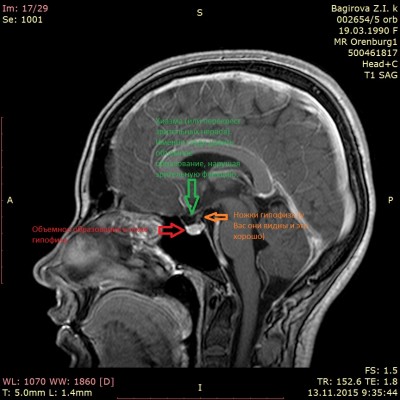

Здравствуйте. Недавно меня проконсультировали в Москве нейрохирурги и сказали, что нужна операция на мозге через нос,чем раньше, тем лучше, нашли у меня опухоль доброкачественную гипофиза. Проверяли гормоны, опухоль гормонально неактивная. Сил уже моих нет. Если есть показания можно ли её удалить в вашей клинике? И что для этого нужно? У меня головные боли просто разрывают голову ежедневно. Не высыпаюсь, перепады настроения в день по несколько раз, чёткость зрения ухудшается. Судороги ног по ночам и утром, мышечная слабость порой такая сильная, что я не могу поднять даже собственную руку. Память не просто плохая, её почти нет. Могу спать сутки. Есть МРТ результаты, но выложить здесь не могу, файл не маленький, это видео. Поэтому присылаю пока МРТ, то что выслали мне из Москвы после консультации.